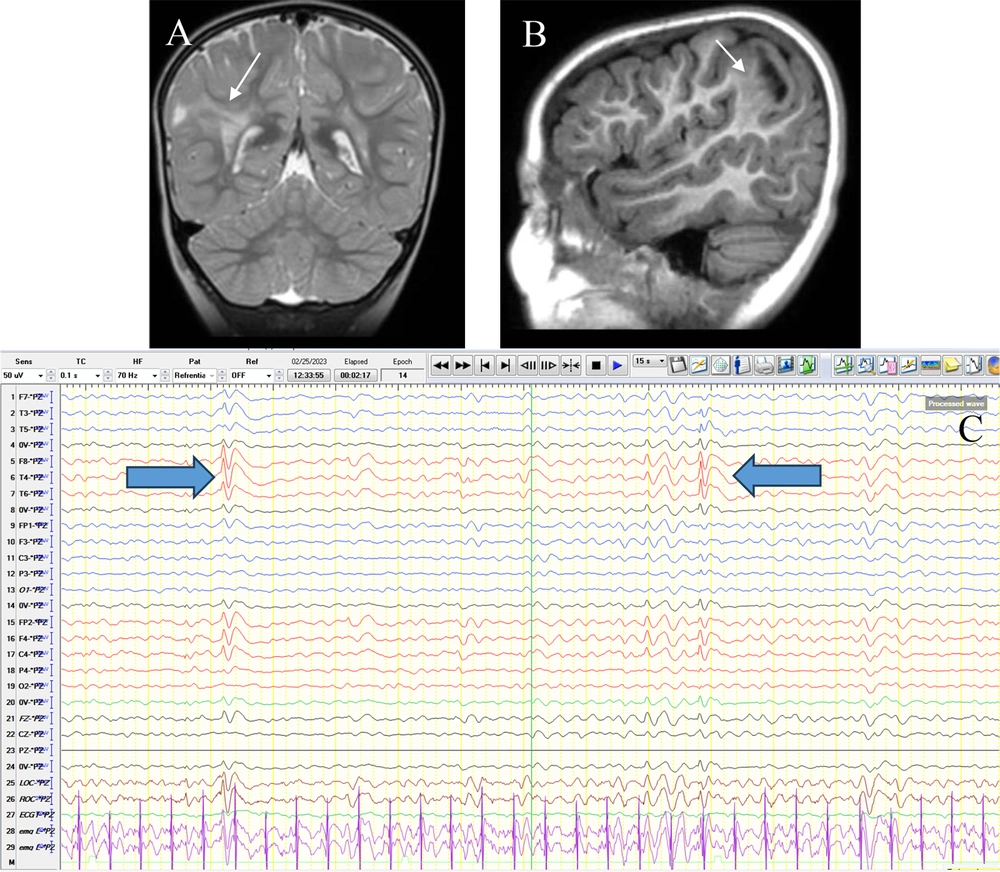

In total, 95 patients with abnormal LTM (53 boys and 42 girls) with an average age of 6.00 ± 3.64 years (ranging from 1 month to 17 years) were included in the study, among whom 59 children (62.1%) had abnormal MRI findings. Baseline characteristics in the two subgroups with and without MRI abnormalities are shown in Table 1. Abnormal neurological examination and prenatal problems were higher in the children with abnormal MRI findings in comparison with those with normal brain MRI (Table 1). As presented in Figure 1, the most common abnormal MRI finding was gliosis (29.3%), followed by focal cortical dysplasia (17.2%) and atrophy (10.3%). Figure 2 shows the most frequent findings in LTM, including left frontal involvement in 17.9%, right temporal involvement in 13.7%, and right frontal involvement in 12.6%. Figure 3 illustrates an instance of consistent abnormality in both LTM and MRI. Out of 95 patients with abnormal LTM, 59 had also abnormal MRI features. In this regard, concomitant right hemisphere involvement in both LTM and MRI was found in 39.0%, concomitant left hemisphere involvement in 28.8%, and involvement of both right and left hemispheres in 18.6% (Table 2). The diagnostic agreement between the MRI and LTM in discovering abnormal findings was found to be high (86.4%) with a kappa correlation coefficient equal to 0.79.

Brain MRI without gad in coronal T2W (A) and sagittal T1W (B) sequences show FCD type IIb with transmantle sign(thin arrow). This trace shows inter-ictal discharges (IEDs) as right-sided (predominantly parietal) polyphasic sharps (thick arrow) predominantly in a referential montage (Pz reference) (C).